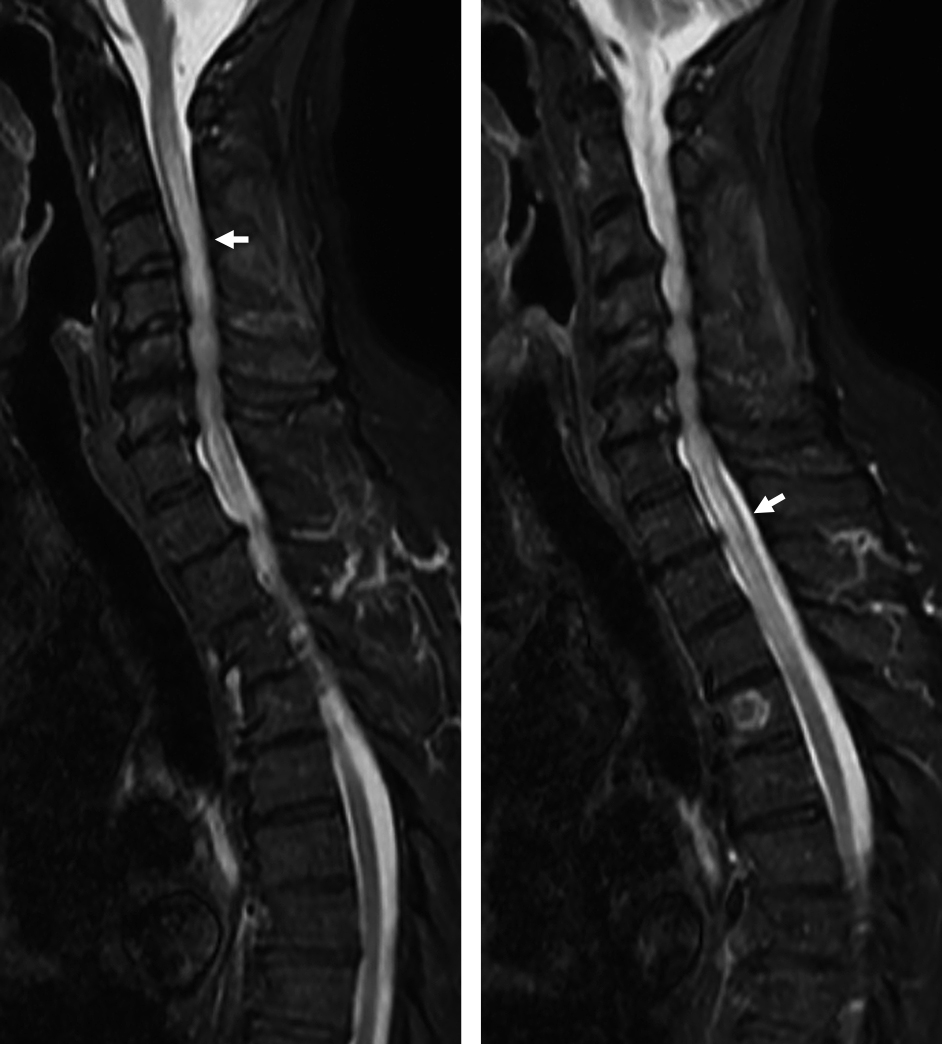

A case of myelin oligodendrocyte glycoprotein antibody-associated disease presenting with radiculopathies

Sunao Takahashi, Takashi Irioka, Ryo Iwase, Susumu Igarashi, Toshiyuki Takahashi